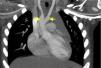

Um rapaz com 2,5 anos apresentou estridor bifásico aos três meses, que agravava com o choro, alimentação e infeções respiratórias altas. Realizou broncofibroscopia (BF) aos cinco meses que diagnosticou traqueomalácia com colapso dinâmico de 80% nos 2/3 inferiores da traqueia. Crescimento normal e sem dificuldade alimentar. Por estridor persistente, a BF aos 21 meses visualizou colapso dinâmico marcado e compressão extrínseca da traqueia. Realizou angiografia por tomografia computorizada (angio‐TC) do tórax, que identificou anel vascular formado por duplo arco aórtico (Figuras 1‐3) responsável por compressão extrínseca sobre a traqueia com franca redução segmentar do seu calibre (Figura 4). Sem outras malformações cardíacas no estudo ecocardiográfico. Aos 23 meses foi submetido a laqueação e divisão do arco mais hipoplásico (anterior esquerdo) por toracotomia. Boa evolução pós‐operatória, mantendo atualmente estridor ligeiro.

Os anéis vasculares representam 1% das cardiopatias congénitas e são a malformação congénita mais frequente com compressão da via aérea. Neste caso a manifestação clínica predominante orientou a sequência de exames de imagem – BF e TC. A combinação de imagens é fundamental na avaliação pré‐operatória. A angio‐TC apresenta vantagens como melhor resolução espacial e temporal, rapidez de aquisição de imagens exigindo apenas sedação/anestesia curta nos doentes não colaborantes, pós‐processamento de imagens com reconstruções tridimensionais e a redução da quantidade de radiação com os equipamentos recentes permite eleger este meio como o preferencial. A avaliação da traqueomalácia ou outro compromisso funcional da via aérea continua a exigir a realização de videobroncoscopia.